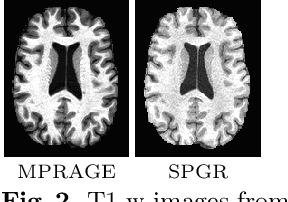

Abstract:Deep learning approaches to the segmentation of magnetic resonance images have shown significant promise in automating the quantitative analysis of brain images. However, a continuing challenge has been its sensitivity to the variability of acquisition protocols. Attempting to segment images that have different contrast properties from those within the training data generally leads to significantly reduced performance. Furthermore, heterogeneous data sets cannot be easily evaluated because the quantitative variation due to acquisition differences often dwarfs the variation due to the biological differences that one seeks to measure. In this work, we describe an approach using alternating segmentation and synthesis steps that adapts the contrast properties of the training data to the input image. This allows input images that do not resemble the training data to be more consistently segmented. A notable advantage of this approach is that only a single example of the acquisition protocol is required to adapt to its contrast properties. We demonstrate the efficacy of our approaching using brain images from a set of human subjects scanned with two different T1-weighted volumetric protocols.